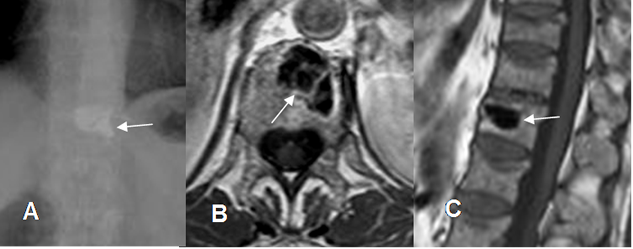

Fig 203. Cambios tratamiento.

A: Rx AP, B: RM axial en T1 y C: RM sagital en T1. Igual paciente anterior. Vertebroplastia con cemento, encontrado como imagen densa en la Rx e hipointensa en la RM.